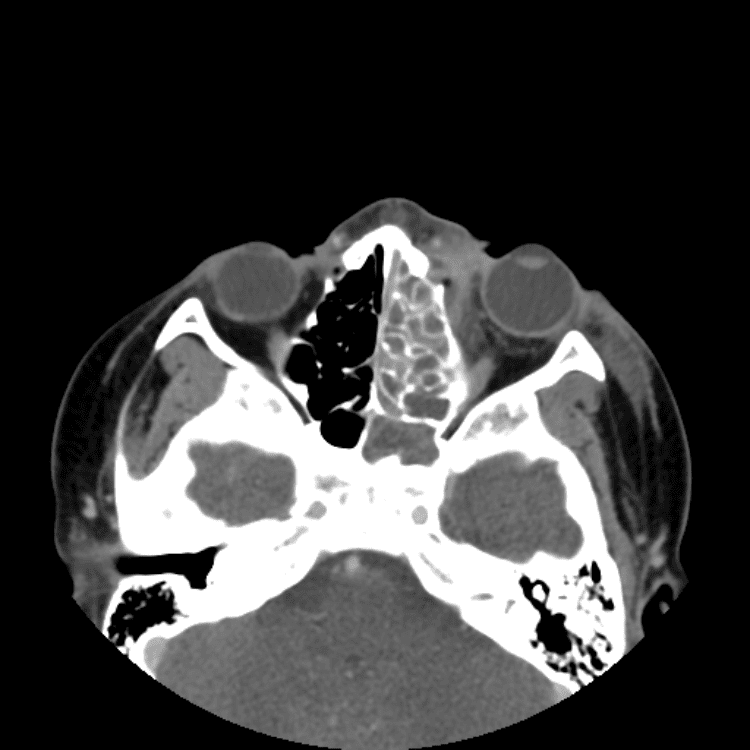

Head and Neck

Simulates call by including subtle or difficult cases and some normals.

27 cases